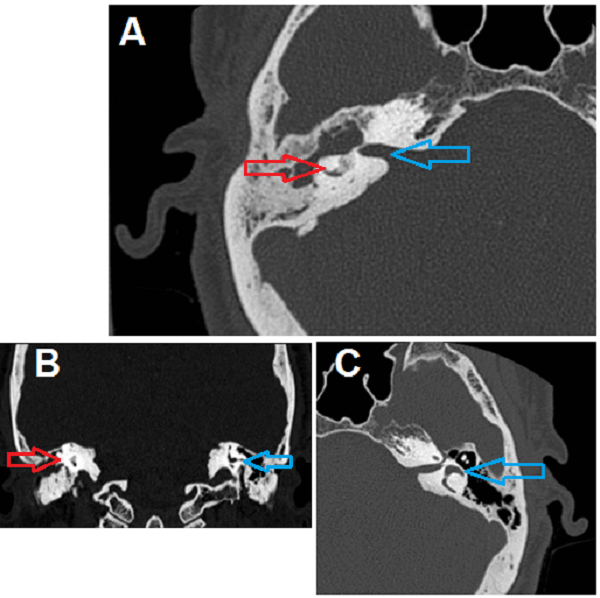

Answer: This cochlea is ossified; the cochlea is normally fluid filled and therefore low density on CT.

(A) axial non contrast CT of the temporal bone demonstrates hyperdensity within the right cochlea (red arrow) consistent with ossification. Compare to the mixed soft tissue/fluid density of the adjacent internal auditory canal (IAC, blue arrow) and the cochlea on the opposite side marked in blue in (B) and (C).